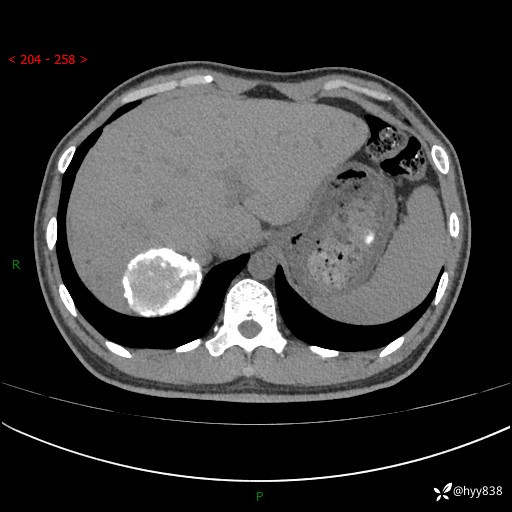

性别:男

年龄:50岁

简要病史:夜尿增多半月,发现肾功能异常1天,超声发现腹膜后占位

腹部CT平扫+增强